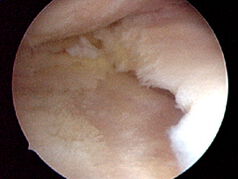

Knorpelschäden:

Knorpelglättung:

hierbei werden aufgefaserte Knorpelanteile vorsichtig geglättet und instabile Knorpelkanten entfernt, um ein Abreisen zu verhindern.

Pridie-Bohrungen:

hierbei werden mit einem Spezialstößel mehrere kleine Löcher in den Knorpeldefekt gebohrt. Durch die entstehende Blutung aus dem Knochen bildet sich ggf. ein Ersatzknorpel. Dieses Verfahren kann auch als „Bioprothese“ angesehen werden.